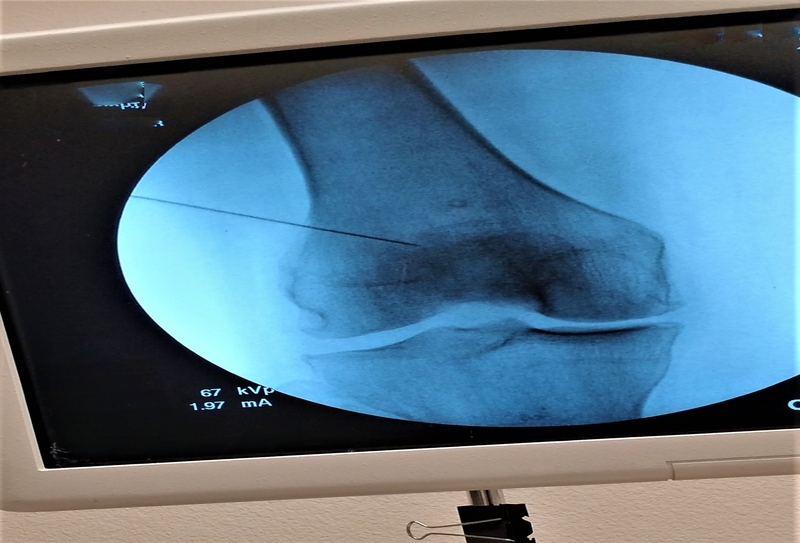

Os joelhos são articulações complexas e que se destacam como uma das partes do corpo mais importantes para a realização de uma atividade corporal, uma vez que se responsabilizam pelo amortecimento dos impactos...

Procedimento de caráter diagnóstico e terapêutico que permite a visualização das estruturas internas no joelho por meio da inserção um dispositivo que carrega uma microcâmera, capta imagens e transmite para um monitor. É uma intervenção pouco invasiva e que possibilita rápida recuperação do paciente.

Indicada para solucionar lesões na fibrocartilagem responsável pelo amortecimento dos joelhos, levando qualidade de vida e conforto aos pacientes. Normalmente é recomendada pelo ortopedista quando as abordagens conservadoras não foram capazes de aliviar o quadro de dor e instabilidade da articulação.